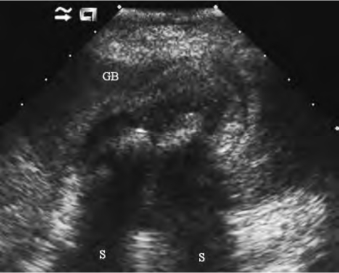

(1)常见表现为胆囊缩小或大小正常,胆囊壁增厚达0.4cm以上,或壁不光滑,毛糙(图25-5)。

图25-5 慢性胆囊炎声像图

图中示胆囊壁明显增厚,内伴结石

(2)胆囊腔内无回声区不清晰,内有多数密集低回声,后回声增强不明显(图25-5)。

(3)常伴有结石超声表现(图25-5)。